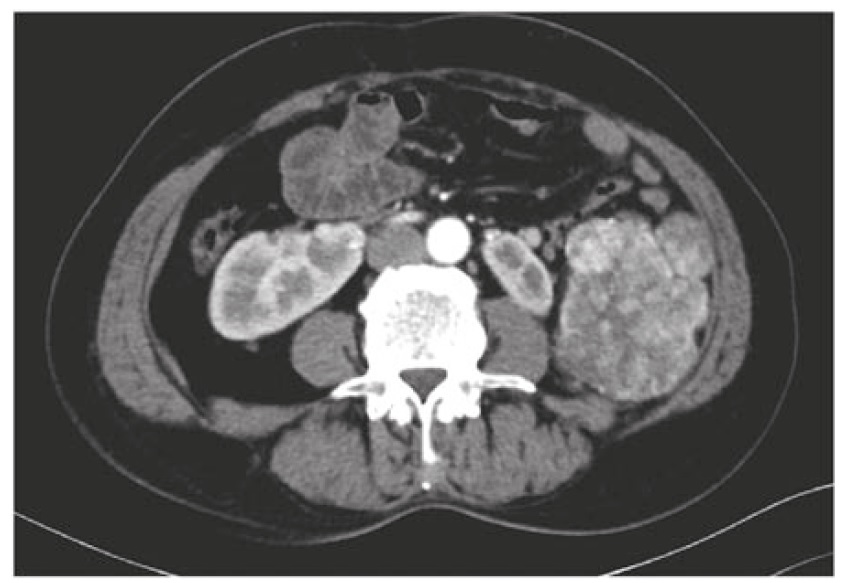

Лучевые и инструментальные методы диагностики, такие как компьютерная томография (КТ), магнитно-резонансная томография, лапароскопия, имеют решающее значение в определении степени распространенности опухоли, при этом необходимо учитывать биологические особенности опухоли (морфологический тип), которые влияют на характер ее роста. При СФО и ДМКО картина КТ характеризуется наличием изолированных узловых образований в любом отделе брюшной полости, которые также могут сопровождаться поражением большого сальника, наличием асцита, увеличением забрюшинных лимфоузлов, возможно отдаленное метастазирование в легкие и кости (рис. 1, 2) [13].

Рис. 1. Десмопластическая мелкокруглоклеточная опухоль [2].

Fig. 1. Desmoplastic small round cell tumor [2].

В целом находки при КТ неспецифичны, однако имеют важное значение при выборе тактики лечения и определения возможного объема операции.